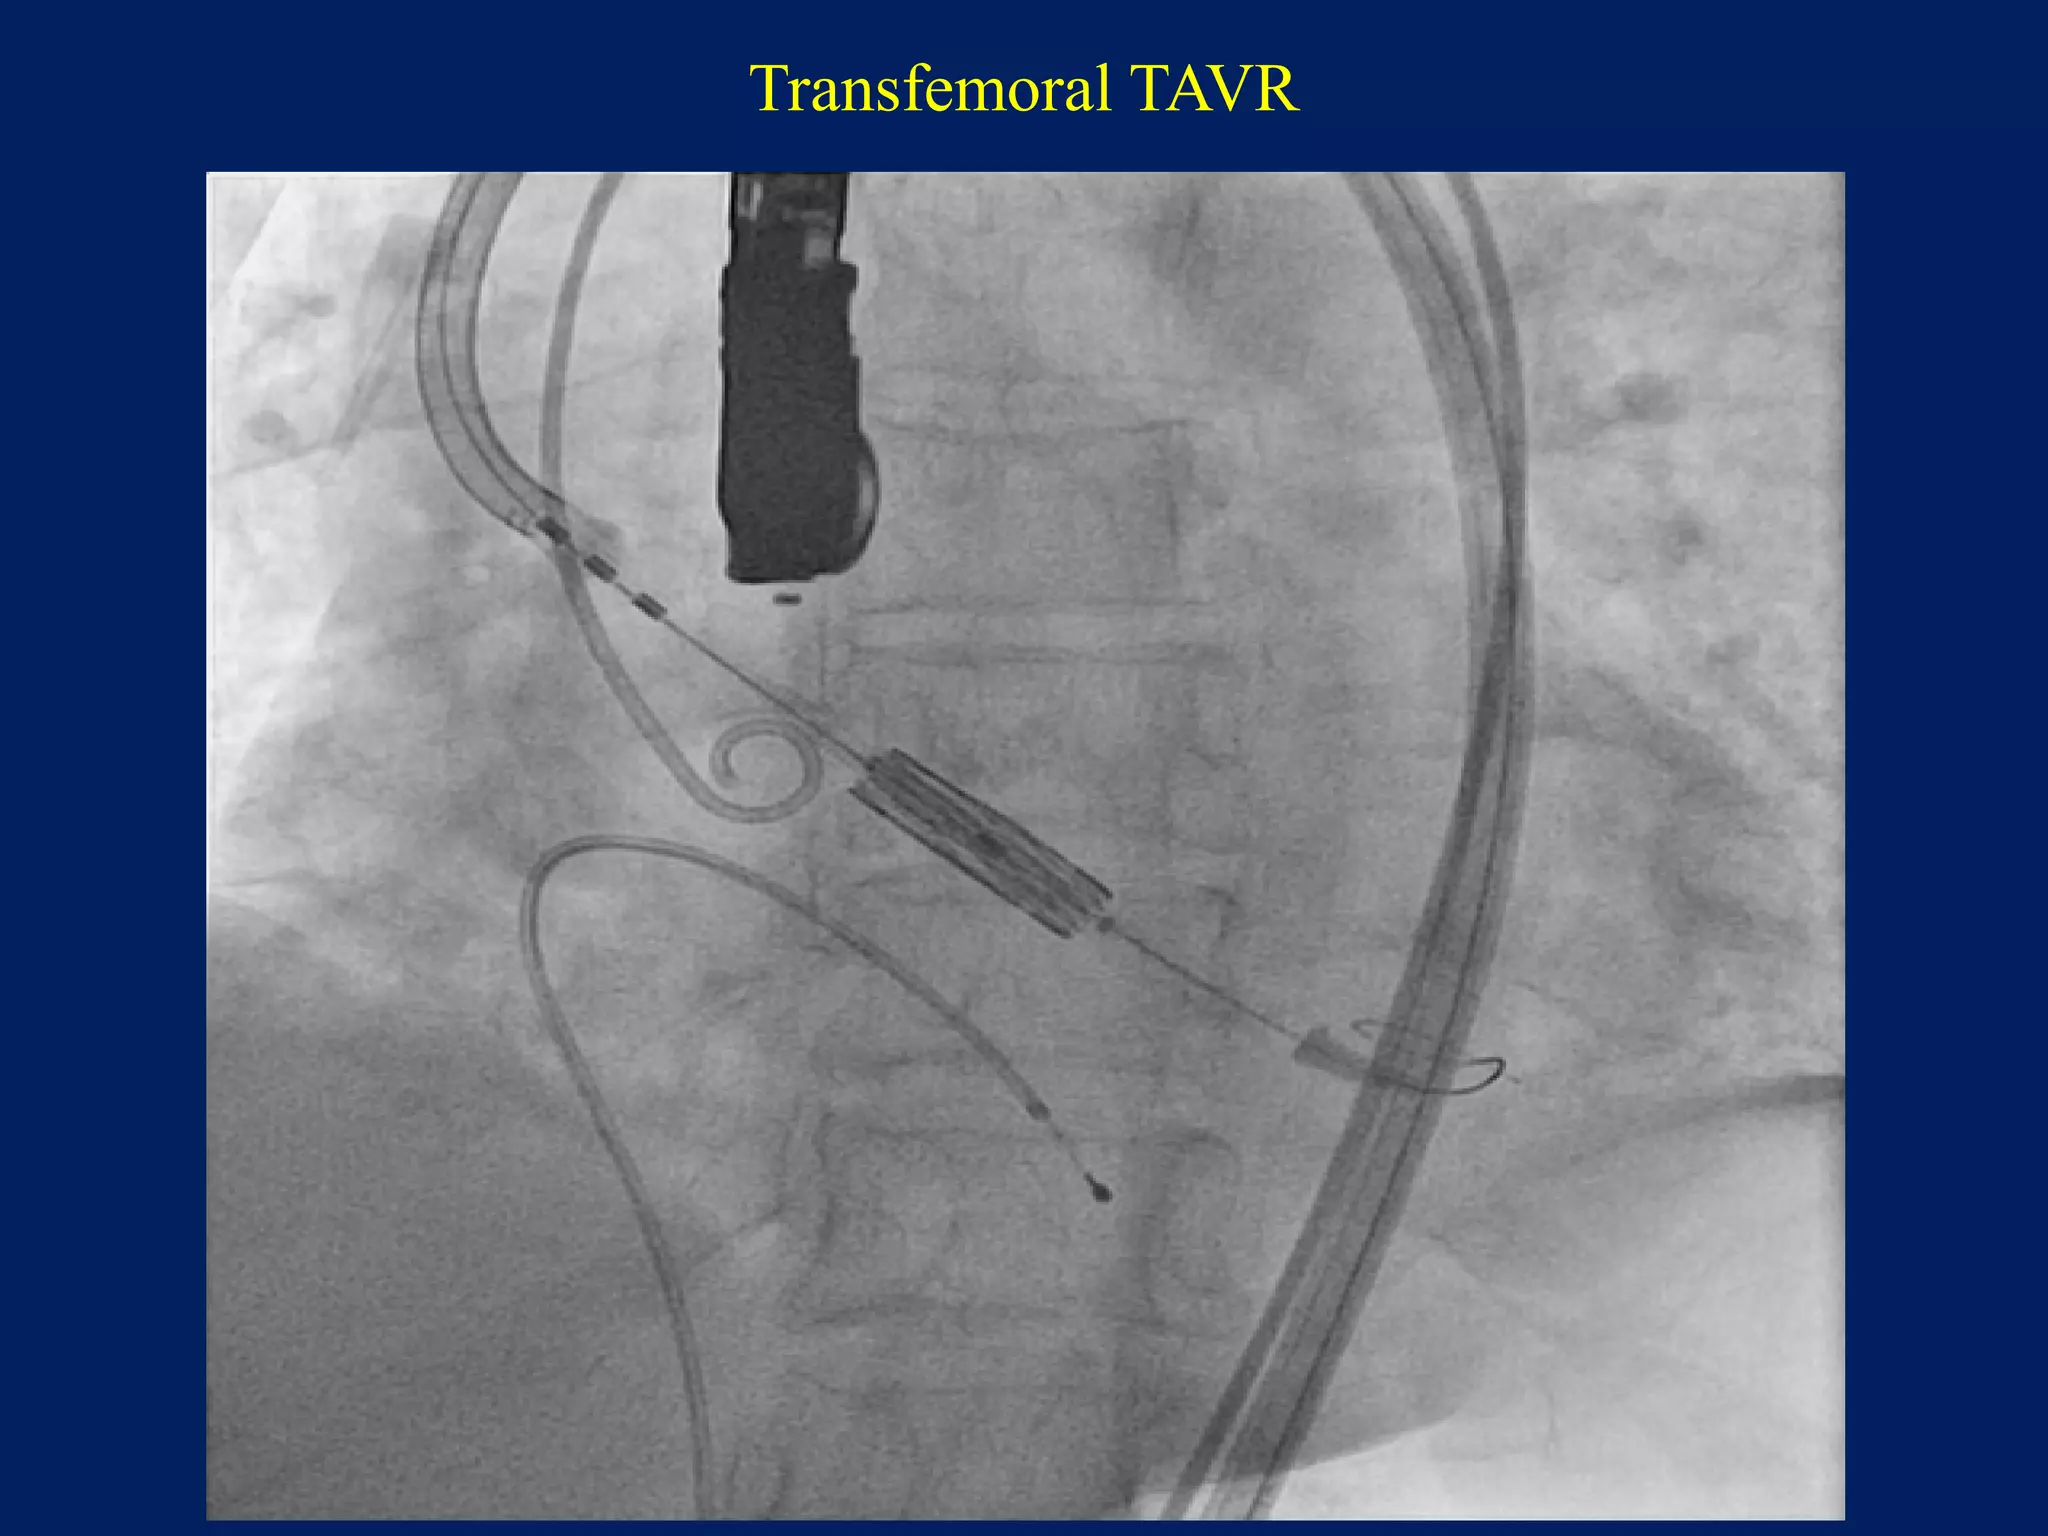

Transfemoral TAVR